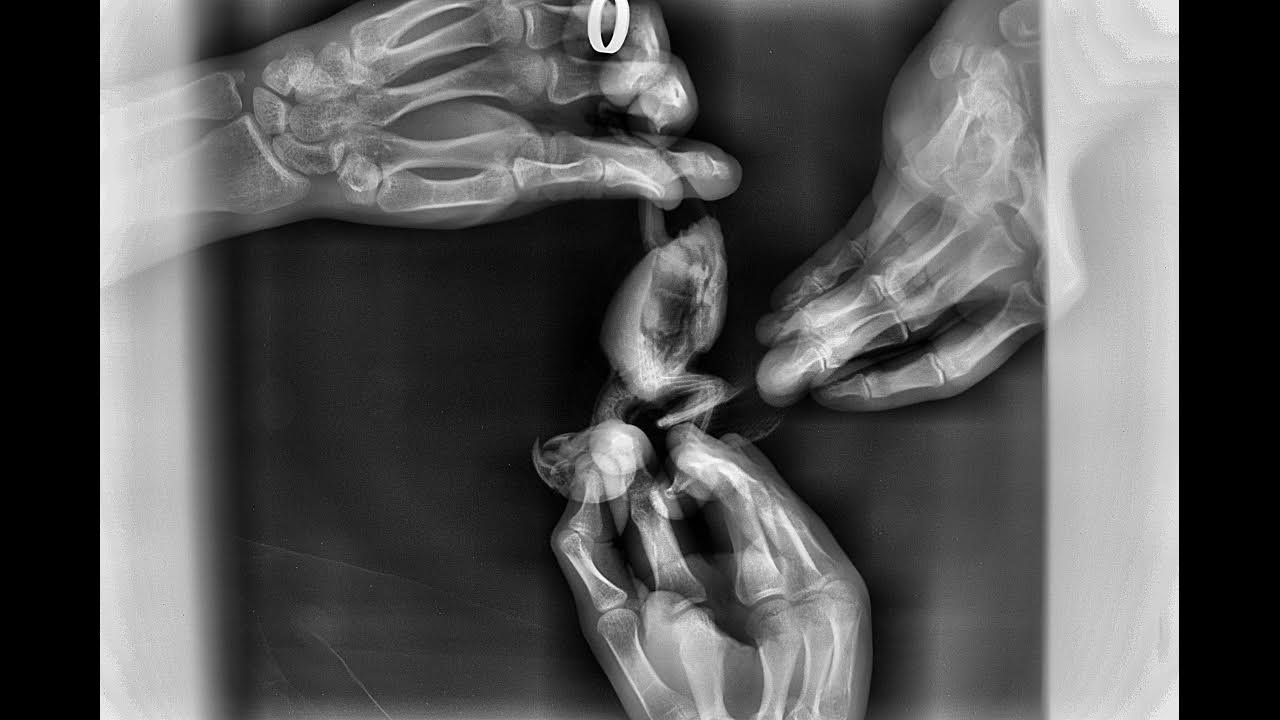

Своеобразное расположение лап и пальцев может говорить, что у птицы был рахит в птенцовом возрасте, и заводчик никак не корректировал проблемы птенца.

Сейчас для изучения существующих проблем очень помог бы цифровой рентген.

Рентген в двух проекциях, основная (на спине), и боковая. Статья Н.Бебих Рентген (если ещё не успели ознакомиться).

@Лилит Сделали сегодня рентген, получилось только в боковой проекции, на спине сделали, но как на зло программа сломалась, начала выдавать ошибки и снимок не удалось сохранить. Пробовали 2 раза, и больше не стали мучить птичку. Рентгенолог сказал, что ничего страшного не видит на снимках.